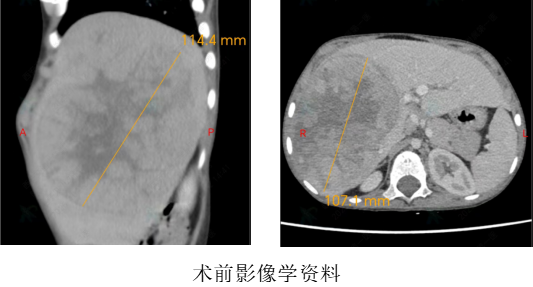

Several months earlier, the child presented with a visibly protuberant right upper abdomen and a palpable hard mass. CT at a local hospital in Shiyan City, Hubei Province, revealed a large hepatic space-occupying lesion measuring approximately 14 × 9 × 15 cm, with a diagnosis of hepatoblastoma. After three cycles of neoadjuvant chemotherapy yielded suboptimal results, the patient sought care at the Department of Pediatric Surgery of the FAH of XJTU.